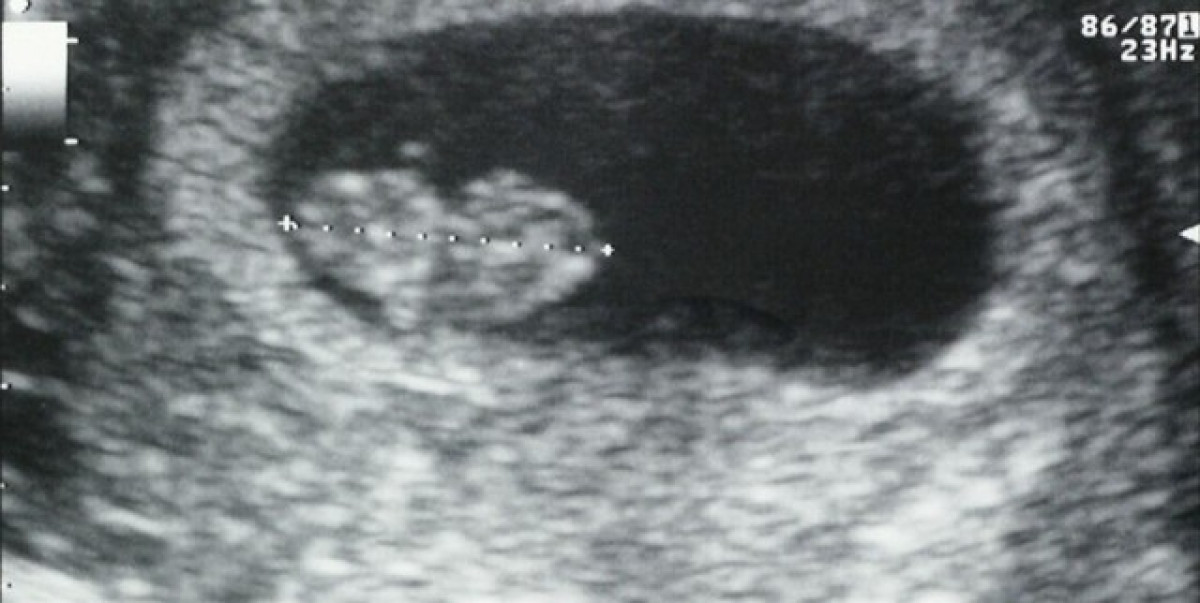

Al seu retorn a Espanya, un examen de rutina va revelar la mort del fetus, la qual cosa s'estima va ocórrer a la setmana 8 de gestació, i l'equip va poder aïllar el virus a la placenta i teixit embrionari, i identificar la placenta com un dels teixits diana del virus.